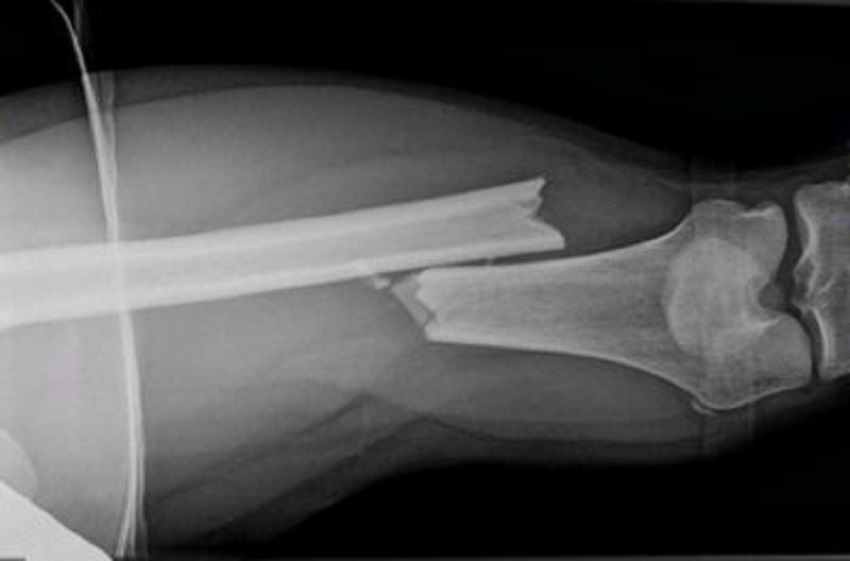

hund x ray zeigt schräge tibial fraktur cranial view – broken leg xray stock-fotos und bilder

Hund X Ray zeigt schräge Tibial Fraktur Cranial View

Hunderöntgenaufnahme mit schräger Tibialfraktur kranialer Ansicht.